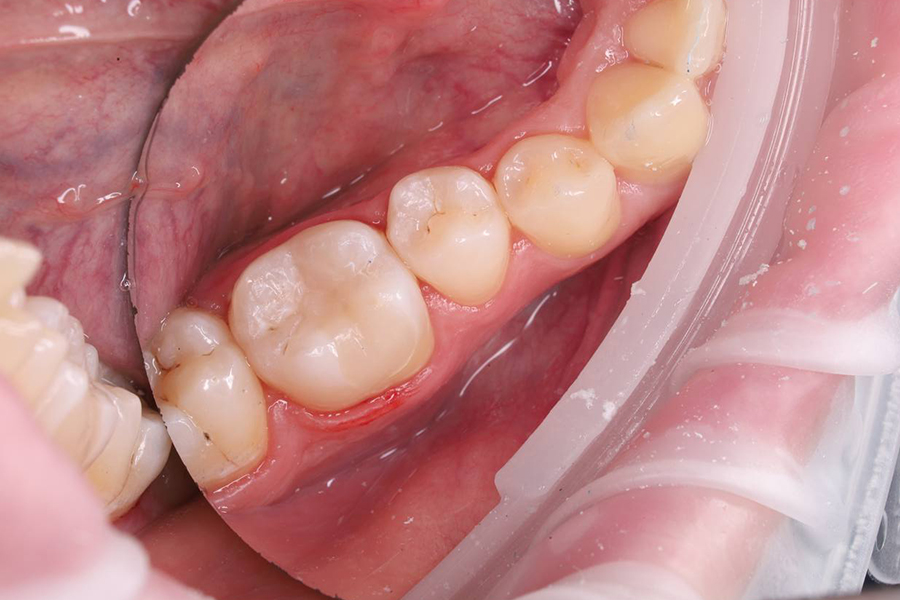

2. Коррекция пломбы по прикусу, полировка.

• Постановка анатомической светоотверждаемой пломбы.

Результат

Пациент доволен результатом, зуб после лечения не беспокоит.